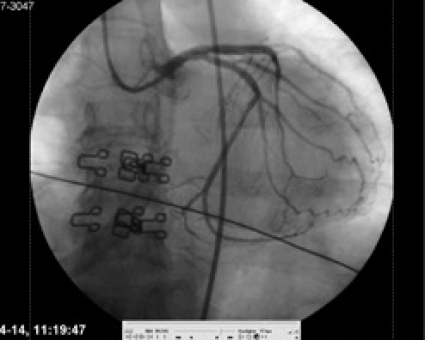

Sinusrytm men kardiogen chock. Patienten var då i kardiogen chock med mycket svaga pulsar spontant. Pulsarna blev åter starka när LUCAS kopplades på igen. Trots dålig prognos beslutades att omedelbart föra patienten till koronarangiolaboratoriet för direkt perkutan koronarintervention (PCI) under pågående LUCAS-behandling. Tre minuter efter ankomst dit punkterades höger a femoralis, kort därefter katetriserades vänster huvudstam. En ocklusion i den främre nedåtstigande grenen (LAD) konstaterades (Figur 1). Tio minuter senare hade ocklusionen dilaterats och stentats till bra resultat (Figur 2). Fullgott flöde (TIMI 3) rådde i kärlet. Patienten fick en reperfusionsarytmi i form av kammarflimmer, som defibrillerades till sinusrytm på första försöket med 200 J. Direkt efter detta var patientens spontana blodtryck ca 60 mm Hg, men efter ytterligare 5 minuter med LUCAS-behandling var det spontana blodtrycket 125/70 mm Hg. LUCAS-behandlingen avslutades.